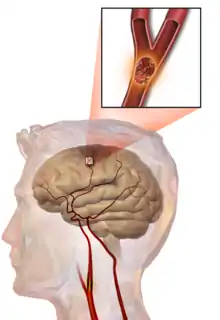

Embolic stroke

An embolic stroke refers to an arterial embolism (a blockage of an artery) by an embolus, a traveling particle or debris in the arterial bloodstream originating from elsewhere. An embolus is most frequently a thrombus, but it can also be a number of other substances including fat (e.g., from bone marrow in a broken bone), air, cancer cells or clumps of bacteria (usually from infectious endocarditis).[48]

Because an embolus arises from elsewhere, local therapy solves the problem only temporarily. Thus, the source of the embolus must be identified. Because the embolic blockage is sudden in onset, symptoms are usually maximal at the start. Also, symptoms may be transient as the embolus is partially resorbed and moves to a different location or dissipates altogether.

Emboli most commonly arise from the heart (especially in atrial fibrillation) but may originate from elsewhere in the arterial tree. In paradoxical embolism, a deep vein thrombosis embolizes through an atrial or ventricular septal defect in the heart into the brain.[48]